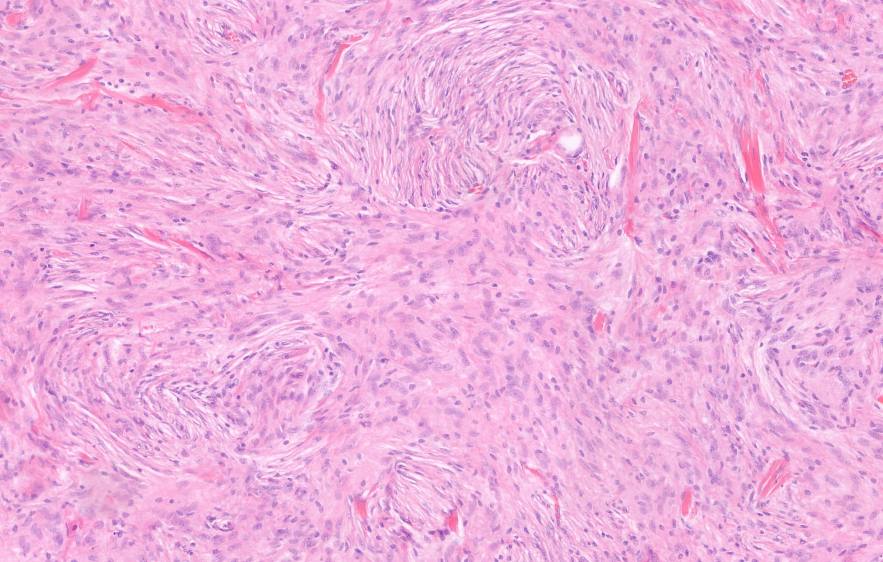

Die Neuropathologie beinhaltet die histopathologische Diagnostik von Läsionen des zentralen und peripheren Nervensystems sowie der Skelettmuskulatur. Wir bieten die differenzierte Klassifikation von Tumoren des ZNS, entzündlichen und degenerativen Erkrankungen unter Einbezug immunhistochemischer und molekularer Marker. Unsere Befunde liefern eine wesentliche Grundlage für neurochirurgische und neuroonkologische Therapieentscheidungen.